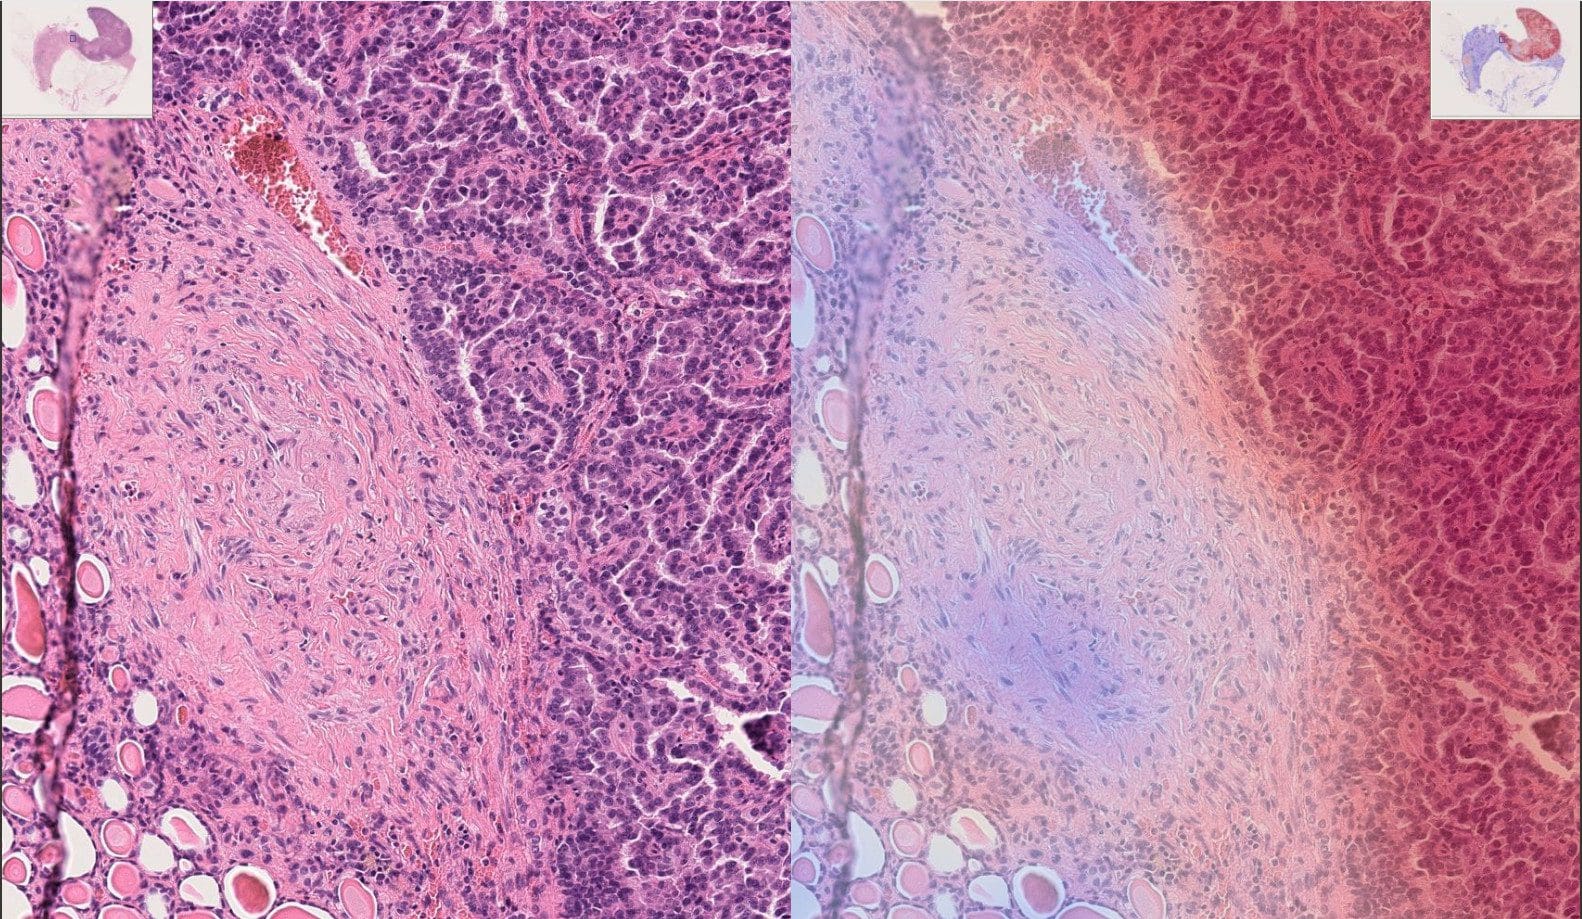

As you can see on the image on the right, the AI support system highlights the regions of high risk where cancer cells are more likely to be. This eliminates the need to physically analyze the whole image of a kidney, providing hints for medical expertise and attention. Similar heatmaps are used for even closer and more high resolution analysis of kidney tissue.

Example of WSI kidney tissue in high resolution (left), with the AI-predicted attention heatmap on the right; Blue color indicates low cancer risk zones, red — high risk.

The advantage of such systems is not only in operational speed and greater accuracy of analysis. The image can also be manipulated in different ways to provide a fuller picture for diagnostics and to make more accurate surgical decisions if needed. You can check the live demo of kidney tissue WSI analysis to see how the interface looks and how exactly it works.